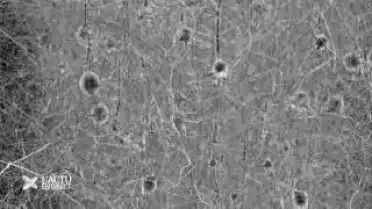

EPFL : des millions pour la recherch sur le cerveau

00:00:00

28.01.2013